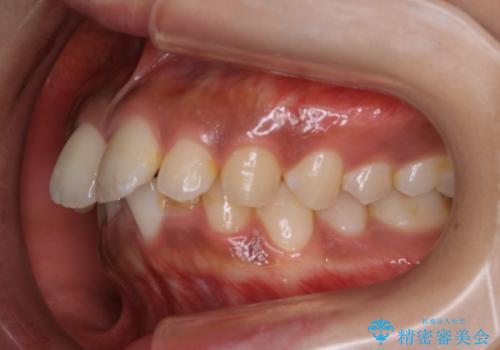

インビザライン矯正 歯を抜かずに出っ歯を改善!

- 出っ歯と前歯の隙間が空いていることを気にされて来院されました。

また、自然な感じで口元を下げていとのことでした。

奥歯のかみ合わせが問題なかったため、上顎の前歯の隙間を閉じるとともに、上顎の歯の側面を削ることをメインにして、出っ歯を改善する治療計画としました。

上顎の歯の傾きを変えるうえで、下顎の歯とのバランスのことも考え、下顎の歯の側面も削ることを加えています。

また、今回は口元を変えたい中に、劇的な変化は避けたいとのことだったので、抜歯をしない計画としています。

抜歯をしない場合、口元の変化は感じにくいですが、前歯の傾きが変わることで、口の閉じやすさは感じていただけたとのことです。

症例にもよりますが、本症例は奥歯のかみ合わせに問題がなかったので歯の側面を削ることメインに、前歯の傾きを改善することができました。

抜歯を行う場合や抜歯をしなくても奥歯の位置をずらす場合は、治療期間が長期化することが多いですが、今回は歯を削ることで改善できたため、短期間で治療を完了することができました。